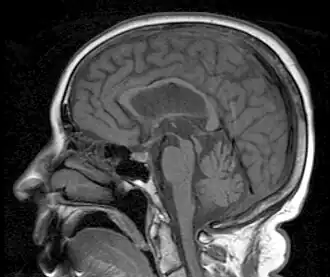

Диагностика клиническая. Дополнительно проводится магнитно-резонансная томография, однофотонная эмиссионная компьютерная томография, позитронно-эмиссионная томография.